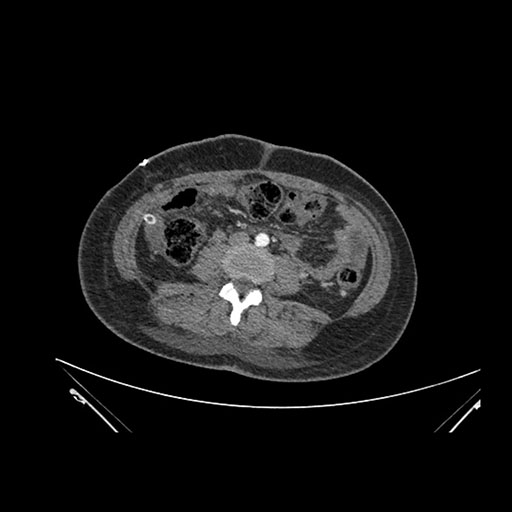

Imaging Analysis

Look through the patient's CT scan to identify any areas of concern for the necessary procedure.

Axial Venous

Based on initial findings, which issue(s) would you be most concerned about?